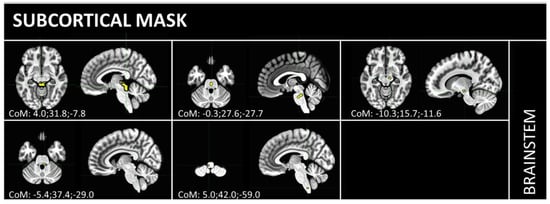

2. Materials and Methods